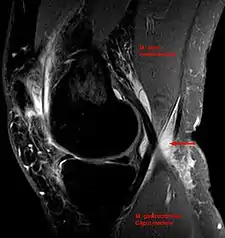

In adults, Baker's cysts usually arise from almost any form of knee arthritis (e.g., rheumatoid arthritis) or cartilage (particularly a meniscus) tear. Baker's cysts in children do not point to underlying joint disease. Baker's cysts arise between the tendons of the medial head of the gastrocnemius and the semimembranosus muscles. They are posterior to the medial femoral condyle.

The synovial sac of the knee joint can, under certain circumstances, produce a posterior bulge, into the popliteal space, the space behind the knee. When this bulge becomes large enough, it becomes palpable and cystic. Most Baker's cysts maintain this direct communication with the synovial cavity of the knee, but sometimes, the new cyst pinches off. A Baker's cyst can rupture and produce acute pain behind the knee and in the calf and swelling of the calf muscles.

Diagnosis is by examination. A Baker's cyst is easier to see from behind with the patient standing with knees fully extended. It is most easily palpated (felt) with the knee partially flexed. Diagnosis is confirmed by ultrasonography, although if needed and there is no suspicion of a popliteal artery aneurysm then aspiration of synovial fluid from the cyst may be undertaken with care. An MRI image can reveal presence of a Baker's cyst.